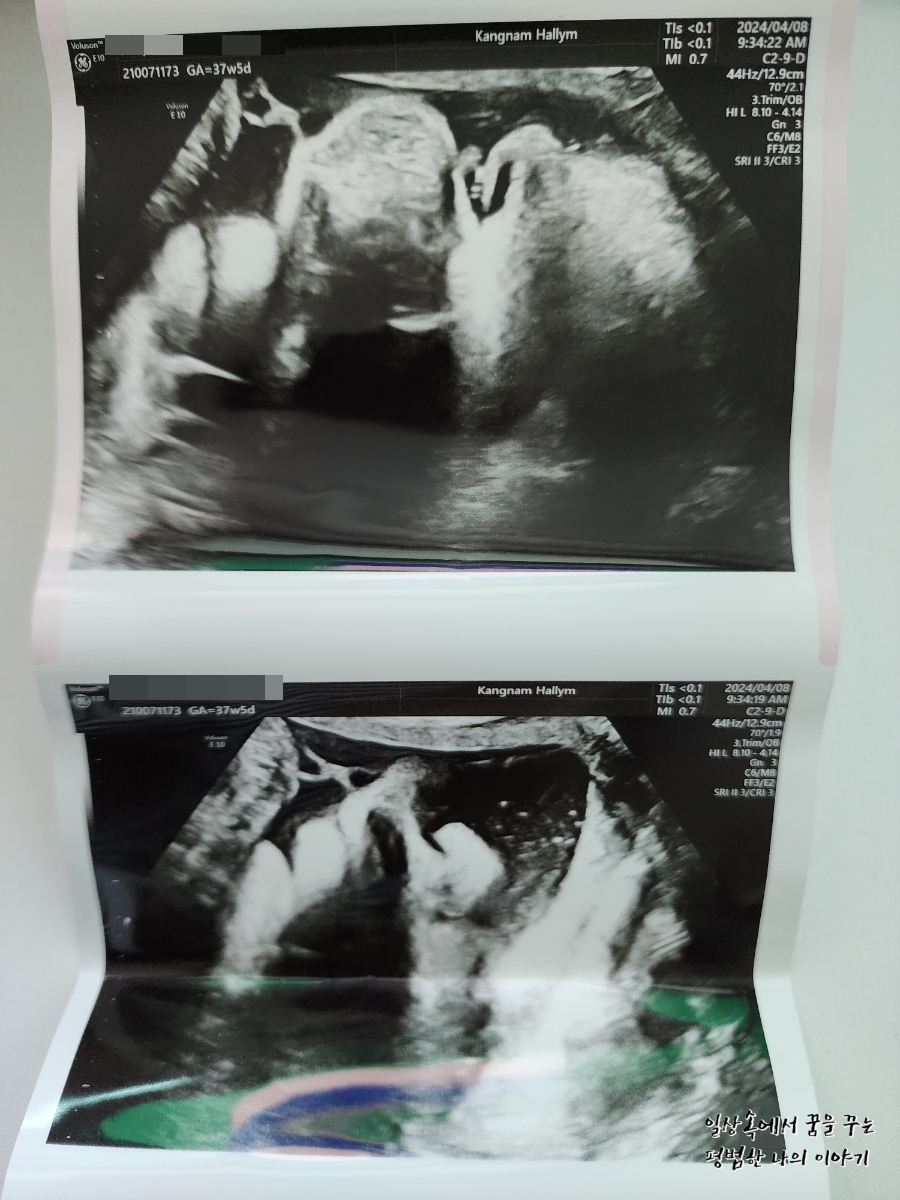

2024년 4월 8일(월요일)

BPD(Biparietal Diameter, 위에서 볼 때 태아 머리 단면의 가장 긴 길이): 9.61cm

HC(Head Circumference, 태아 머리둘레): 34.05cm

AC(Abdominal Circumference, 배 둘레): 37.65cm

FL(Femur Length, 허벅지뼈 길이): 7.22cm

GA(Gestational Age, 임신 주차): 37주 차 5일

EFW(Estimated Fatal Weight, 태아 예상 체중)=EBW(Estimated Body Weight): 4044g

FHR(Fetal Heart Rate, 심장박동 수): 157bpm

CL(Cervical Length, 자궁경부 길이): 정상

AF(Amniotic Fluid, 양수): 정상